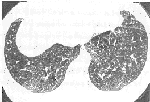

HRCT表现:支气管壁增厚15例(53.6%)(图1),其中5例可见两下叶支气管腔明显变小。支气管扩张6例(21.4%),且均呈轻度柱状支气管扩张,马赛克征象3例(10.7%),纵隔及皮下气肿1例(3.6%)(图2),小叶中心型肺气肿4例(14.3%)且年龄均大于50岁。7例呼气末HRCT中5例(71.4%)可见空气潴留征象(图3)。综合上述所见至少发现一项异常的支气管哮喘患者共20例(71.4%),仅8例(28.6%)未发现任何异常改变。

, http://www.100md.com 图1 支气管壁增厚(箭),未见空气潴留征象